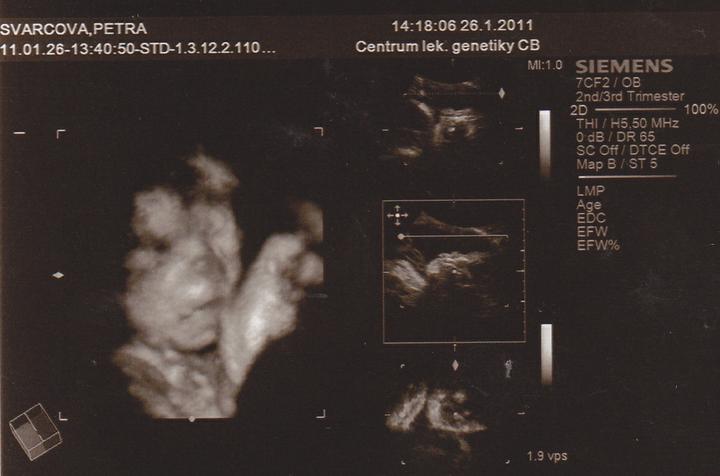

26.1.Jedu do Českých Budějovic na 4D ultrazvuk.Už se nemůžu dočkat.

Včera jsem Byla v Českých Budějovicíh.Jedno mimi váží 267g, a druhé váží 314g.A jsou to kluci.